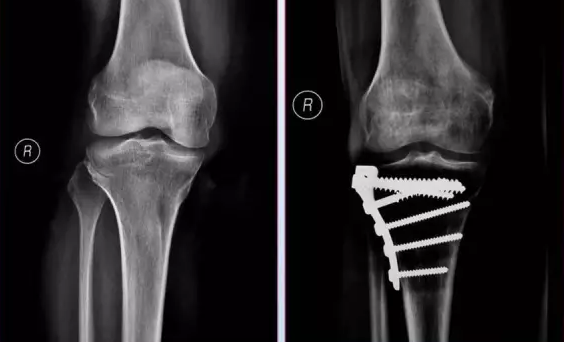

胫腓骨骨干骨折在全身骨折中最为常见。10岁以下儿童尤为多见。其中以胫骨干单骨折最多,胫腓骨干双折次之,腓骨干单骨折最少。

临床上锁定钢板螺钉取出困难时主要表现为螺钉滑丝及钉帽与钢板钉孔间的螺纹错扣。